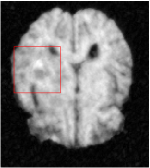

All the experiments are implemented on a Windows workstation with Intel Core i9 CPU at 3.3GHz and an Nvidia GTX-1080Ti GPU with 11GB of graphics card memory via TensorFlow Abadi et al. (2016). The parameters in the proposed network are initialized by using Xavier initialization Glorot and Bengio (2010). We trained the meta-learning network with four tasks synergistically associated with four different CS ratios: 10%, 20%, 30%, and 40%, and test the well-trained model on the testing dataset with the same masks of these four ratios. We have 300 training data for each CS ratio, which amount to total of 1200 images in the training dataset. The results for and MR reconstructions are shown in Tables 5.4 and 5.4 respectively. The associated reconstructed images are displayed in Figures 1 and 3. We also test the well-trained meta-learning model on unseen tasks with radio masks for skewed ratios: 15%, 25%, 35%, and random Cartesian masks with ratios 10%, 20%, 30% and 40%. The task-specific parameter for the unseen tasks are retrained for different masks with different sampling ratios individually with fixed task-invariant parameters . In this experiments, we only need to learn for three skewed CS ratios with radio mask and four regular CS ratios with Cartesian masks. The experimental training proceed on less data and iterations, where we performed on 100 MR images with 50 epochs. For example, for reconstructing MR images with CS ratio 15% radio mask, we fix the parameter and retrain the task-specific parameter on 100 raw data with 50 epochs, then test with renewed on our testing data set with raw measurement that sampled from radio mask with CS ratio 15%. The results associated with radio masks are shown in Table 5.4 and 5.4, Figure 2 and 4 for and images respectively. The results associated with Cartesian masks are list in Table 5.4 and reconstructed images are displayed in Figure 5.

Qualitative comparison between conventional and Meta-learning methods are shown in Figure 1 and 3, which display the reconstructed MR images of the same slice for T1 and T2 respectively, we label the zoomed-in details of HGG in the red boxes. We observe the evidence that conventional learning is more blurry and lost sharp edges, especially in lower CS ratios. From the point-wise error map, we find meta-learning has the ability to reduce noises especially in some detailed and complicated regions comparing to conventional learning.